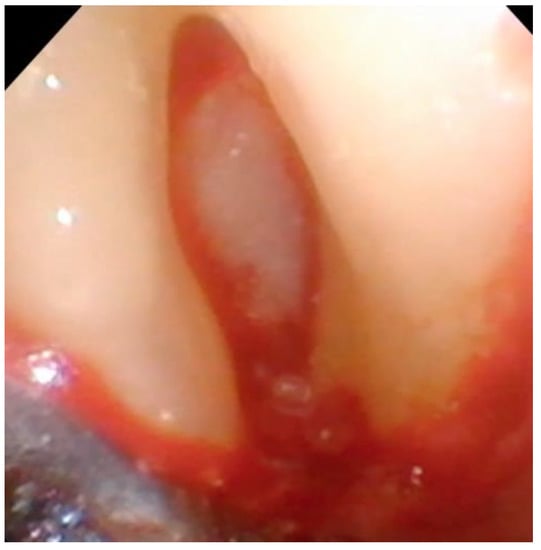

Figure 9. The bony lesion pictured in Figure 8 has been filled with particulate bone-grafting material mixed with EMD.

After the lesion is debrided of granulation tissue and the implant is cleaned with saline, DFDBA mixed with EMD is place in the bony defect. (Figure 9).